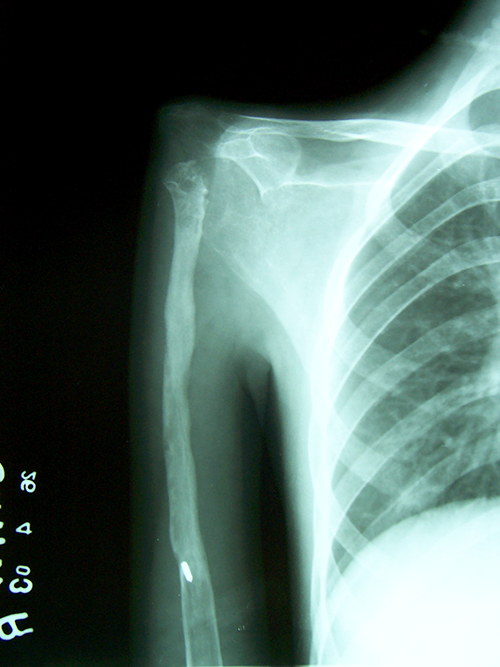

Case:7 GCT Humerus

Pre-Op

3 Years follow-up

5 Years follow-up